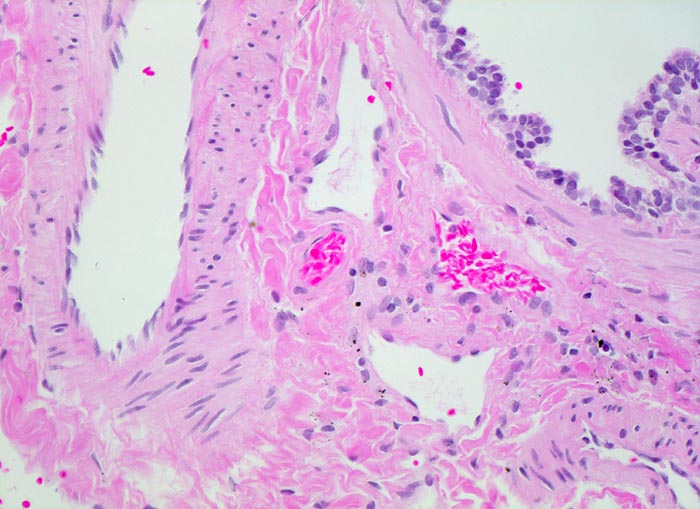

PathoPic ID 4365 - normales Lungenparenchym: Lungenarterienast und Bronchiolus

normales Lungenparenchym: Lungenarterienast und Bronchiolus

Links im Bild ein Ast der Pulmonalarterie. Rechts davon der Anschnitt eines Bronchiolus mit

glattmuskulärer Wand.

200

24

männlich